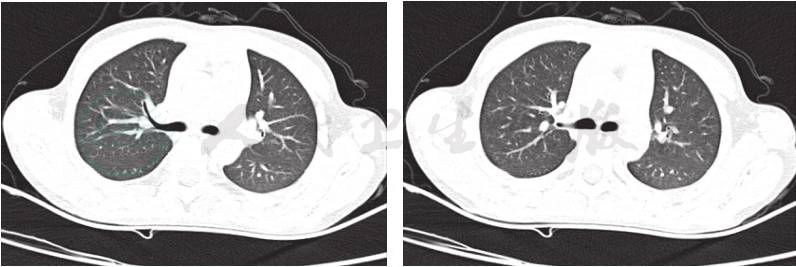

入院第二天行纤维支气管镜检查,镜下可见左肺舌叶(B4、B5)开口处可见一块肿物堵塞大部分管腔(图3),予活检钳钳取部分肿物和留取支气管灌洗液,送病理检查。病理结果回报(图4):(支气管)慢性炎症,局灶见不典型类上皮结节,不除外结核。因此考虑患儿是支气管淋巴结核,结核分枝杆菌突破相邻的支气管内膜,干酪样物进入管腔导致气管腔阻塞。因此增加了抗结核的种类,给予患儿三联抗结核药物(异烟肼、利福平、吡嗪酰胺)口服治疗1个月复查支气管镜。第二次支气管镜下舌叶(B4、B5)开口处可见(图5)黄白色干酪样物质周围被肉芽组织包裹完全堵塞其开口,先用活检钳反复钳取黄白色干酪样物质,并将钳取物分别涂片镜检并送活组织病理检查,考虑常规口服抗结核药物渗透到支气管内膜的浓度小,对局部治疗效果差,因此取了病理后对肉芽组织以及干酪样物进行4次冷冻治疗(每次冷冻时间30~60秒不等)和反复多次钳取,治疗结束后,B5支气管开口得以暴露(图6),其支气管管腔开口通畅,可见正常B5亚段结构,但B4支气管开口仍被肉芽组织覆盖(图7)。分别在第2天后、2周后、1个月后、2.5个月后、6个月后进行5次支气管镜下钳取和冷冻治疗。6个月后第七次支气管镜显示,镜下可见左肺舌叶B5开口通畅,舌叶B4开口形成瘢痕狭窄,2.8mm支气管镜可通过,远端亚段结构正常。复查肺CT可见(图8):左肺上舌叶片状高密度影基本吸收,左肺门肿大淋巴结影较前略减小。

图3 入院后第一次完善纤维支气管镜检查